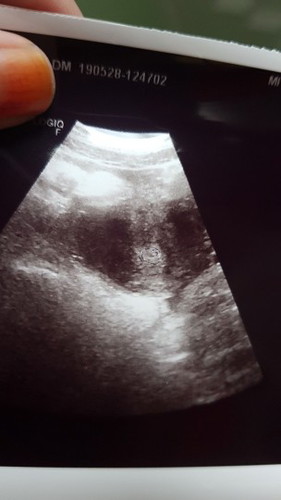

usg 6 weeks dari hpht ada yg paham gak?

Ini terlalu kecil atau memang wajar? Yg tau jawab ya bunda2... yg mau share usg 6 weeks nya juga boleh